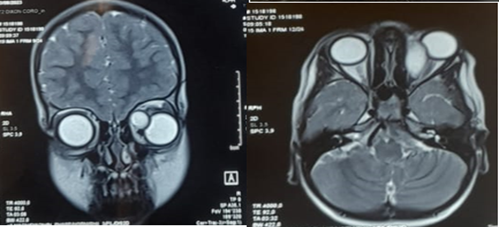

Orbital CT and MRI were performed

CT imaging revealed a well-defined mass, approximately 3 cm in size, enhanced by contrast, causing grade III exophthalmos without globe invasion or evidence of bone erosion. MRI showed a well-demarcated left intraorbital lesion, hypointense on T1-weighted images and hyperintense on T2-weighted images, suggestive of a benign hydatid cyst. The patient underwent surgical excision of the lesion. Histopathological analysis confirmed the diagnosis of a hydatid cyst. Postoperative clinical evolution of the left eye was marked by a gradual resolution of inflammatory signs and regression of the exophthalmos.

Figure 2: Axial and frontal section of T2 MRI showing the orbital cyst